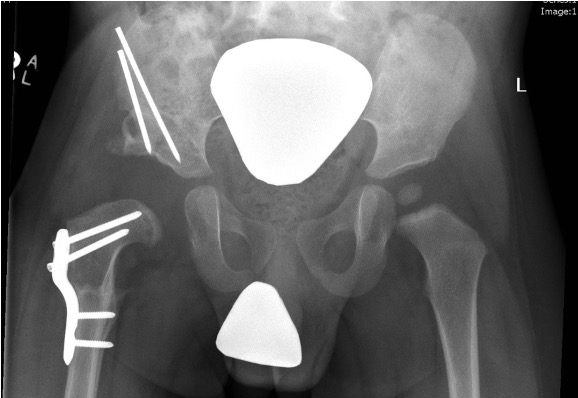

Salter complete osteotomy